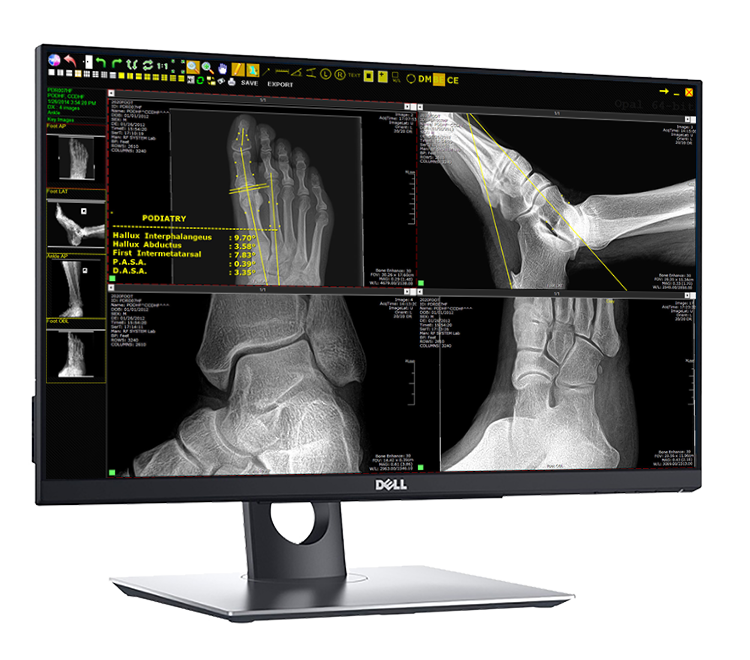

Dell Server PC (Full PACS)*

Dell 24" LED IPS 2MP Touchscreen Monitor

- 10-point Touchscreen

- High Quality Display for optimized viewing

- VESA Wall-mount compatible

Opal-RAD Software

Multi-functional Studylist (see above)

- Burn/Import CDs

- Compare images (post/pre op)

- Custom search/query

- Customize user privileges

Acquisition (see above)

- Processing Technology: sharper images, clarity

- Auto Contrast upon processing

- Image auto-shutter/crop

Viewer (see left)

- User friendly, DICOM compliant, DPM Tools ††

- 5 additional viewing licenses included

- WORLDWIDE access: view from anywhere!*

Podiatric Tool-Set††

- Hallux Interphalangeus

- Hallux Abductus

- First Intermetatarsal

- P.A.S.A.

- D.A.S.A.

- Metatarsus Adductus

- Total Adductory Angle

- Metatarsal Parabola

- Metatarsal Protrusion

- Talo-Calcaneal